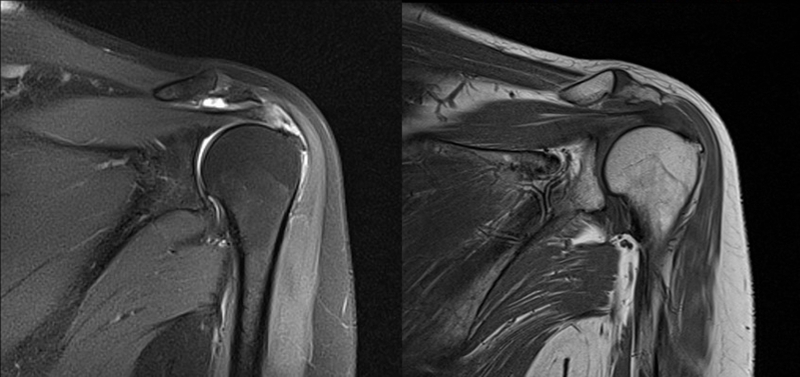

2、MRI检查

MRI目前是诊断肩袖疾病中最常用的检查,可以直观的观察肩袖肌腱。

图21 斜冠状位(临床常用)a.T2,b.T1

图22 斜矢状位 a.冈上肌出口,肩袖诊断不如斜冠状位;b.冈上肌及肌腹脂肪浸润成度,评估手术与否